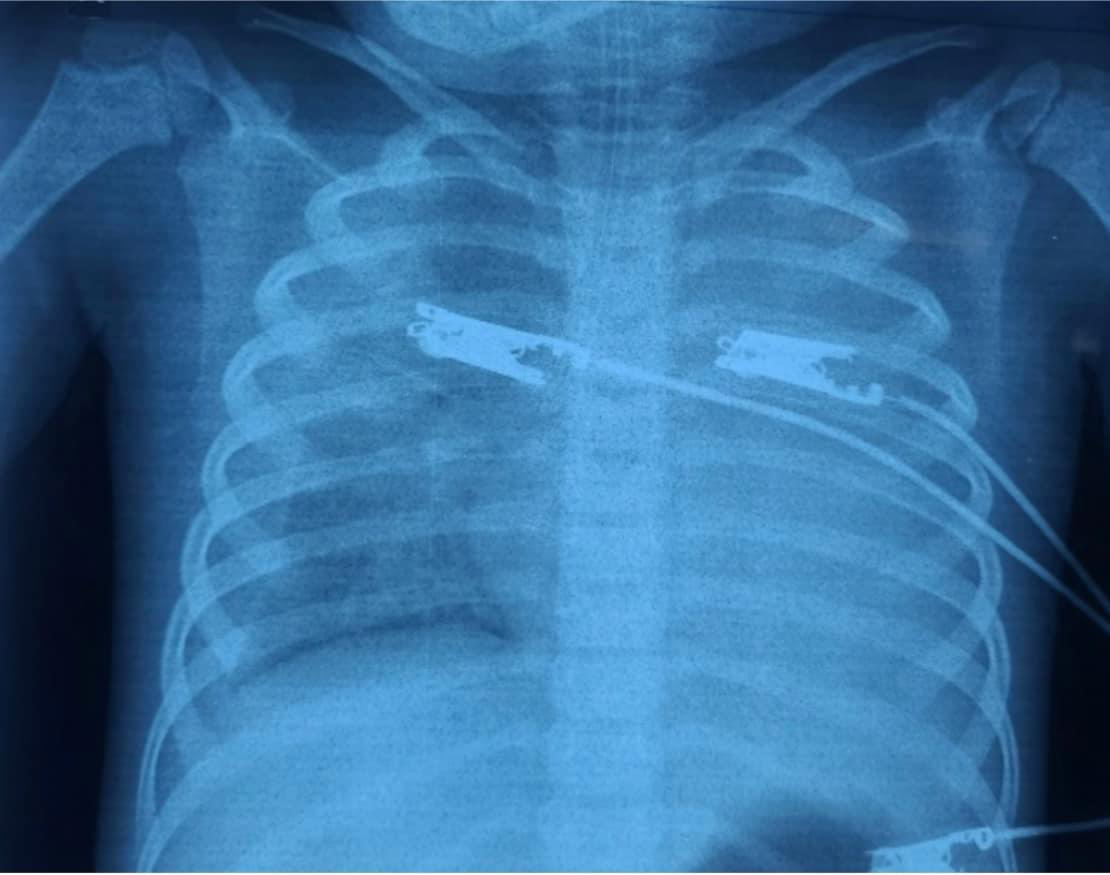

PGS.TS.BS Phùng Nguyễn Thế Nguyên, Trưởng khoa Hồi sức Nhiễm, Bệnh viện Nhi đồng 1 cho biết, bệnh nhi nhập viện trong tình trạng thiếu máu nặng (dung tích hồng cầu 16%), gan to 4 cm dưới hạ sườn phải và lách to độ 4. Các xét nghiệm tại cấp cứu cho thấy bệnh nhi nhiễm khuẩn nặng, tổn thương phổi và tràn dịch màng phổi phải; tổn thương phổi với hội chứng nguy kịch hô hấp cấp do viêm lan toả 2 phổi, tuỷ đồ có hình ảnh thực bào máu.

![]() |

| Hình ảnh phổi bệnh nhi bị tổn thương. Ảnh: BV |